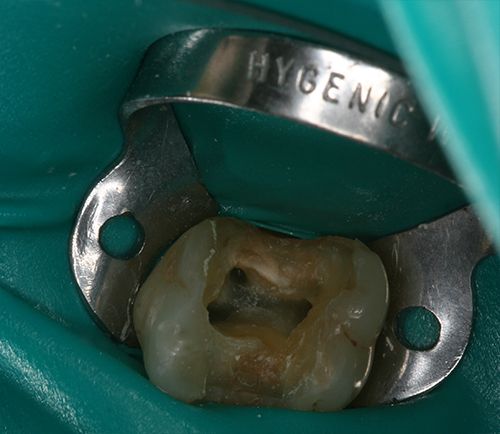

- Εκτεταμένη / βαθιά τερηδόνα, η οποία έχει διαπεράσει την οδοντίνη και έχει προσβάλλει τον πολφό (νεύρο του δοντιού).

- Τοποθετείται ένα ειδικό λάστιχο, που λέγεται απομονωτήρας

- Ακολουθεί η διάνοιξη του δοντιού και η εύρεση των ριζικών σωλήνων (ριζών του δοντιού)